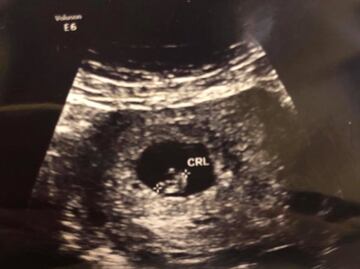

El segundo hijo de Fernando Purón Johnston será un niño, reveló Cynthia Villarreal , viuda del ex alcalde de Piedras Negras y candidato del PRI a diputado federal.

"Fernando Gastón Purón Villarreal viene en camino y seguirá dejando huella!!! #MiRey #MiNiño #FamiliaPurónVillarreal #GraciasDios", publicó en su perfil de Facebook.

Cynthia escribió su mensaje junto a una fotografía donde está con su hijita María Constanza y un puñado de globos en distintos tonos de azul y blanco.

El pasado 17 de junio y con motivo del Día del Padre , Cynthia Villareal reveló a través de la misma red social que estaba embarazada de su segundo hijo.